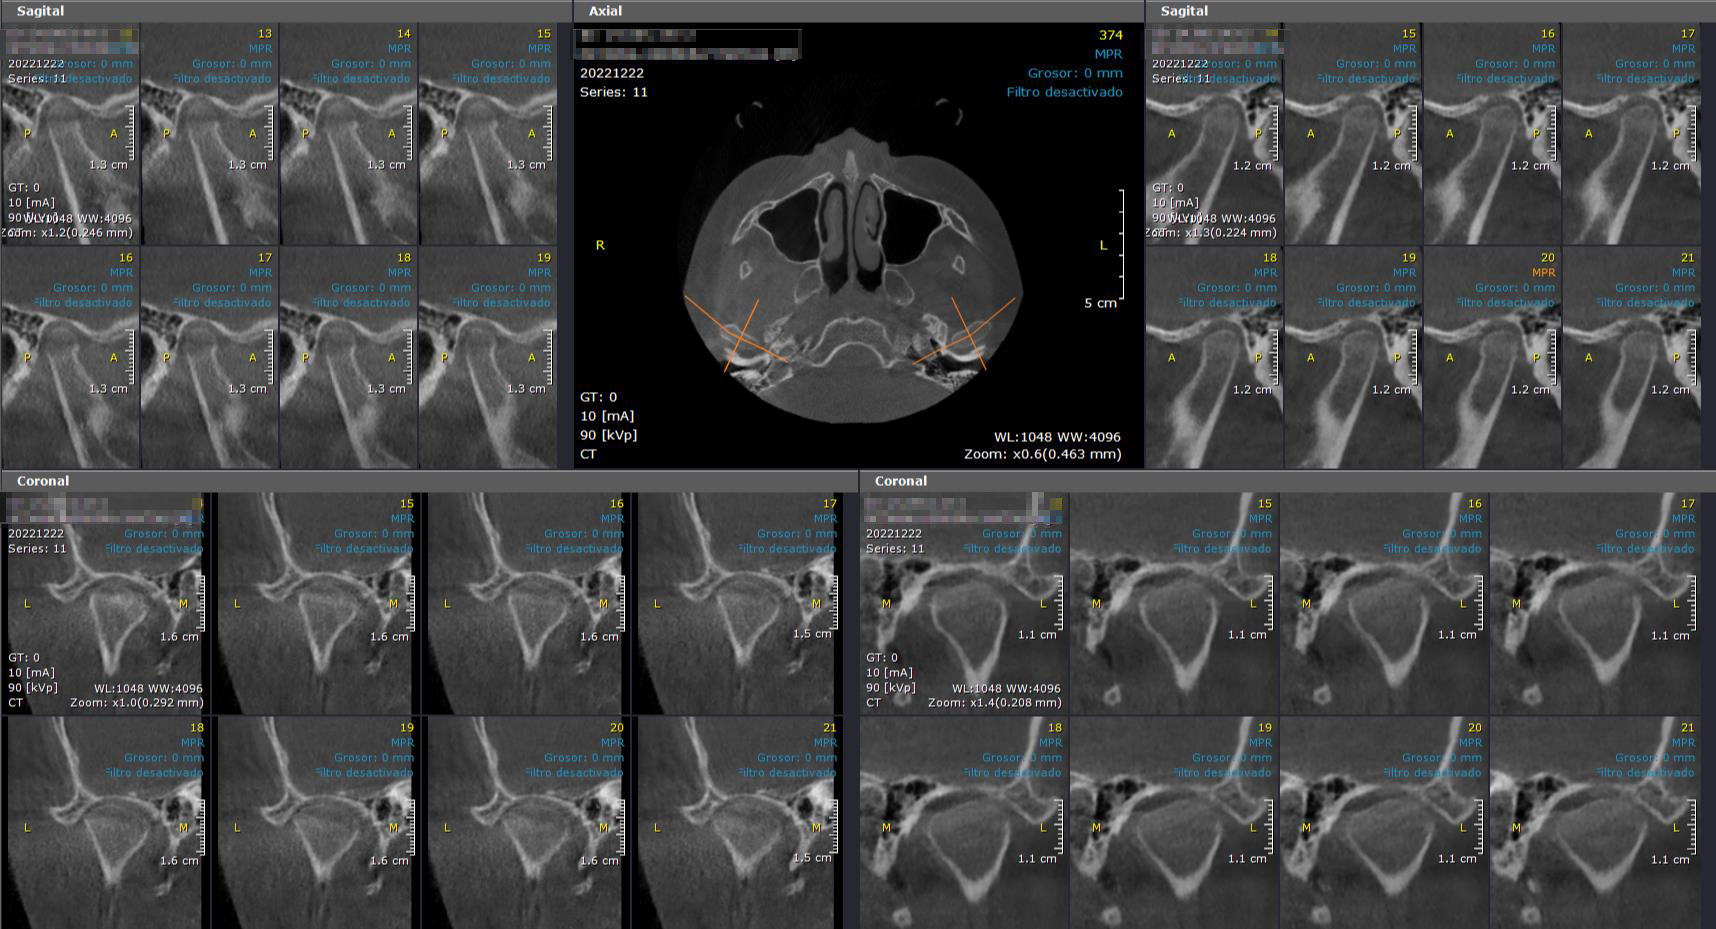

Evaluación Implantes:

Maxilar/ Mandibular/ Bimaxilar/ Orbitomaxilofacial

Estudio Localización:

Traumatismo/ Patología Ósea

Estudio Endodoncia Diente (S)

Estudio Ortodoncia:

Incluye Reconstrucción Panorámica, Telerradiografía 3D Lateral y Frontal; Modelos Oclusión 3D, ATM Bilateral y Vía Aérea Superior 3D

Articulación Témporo Mandibular (ATM)